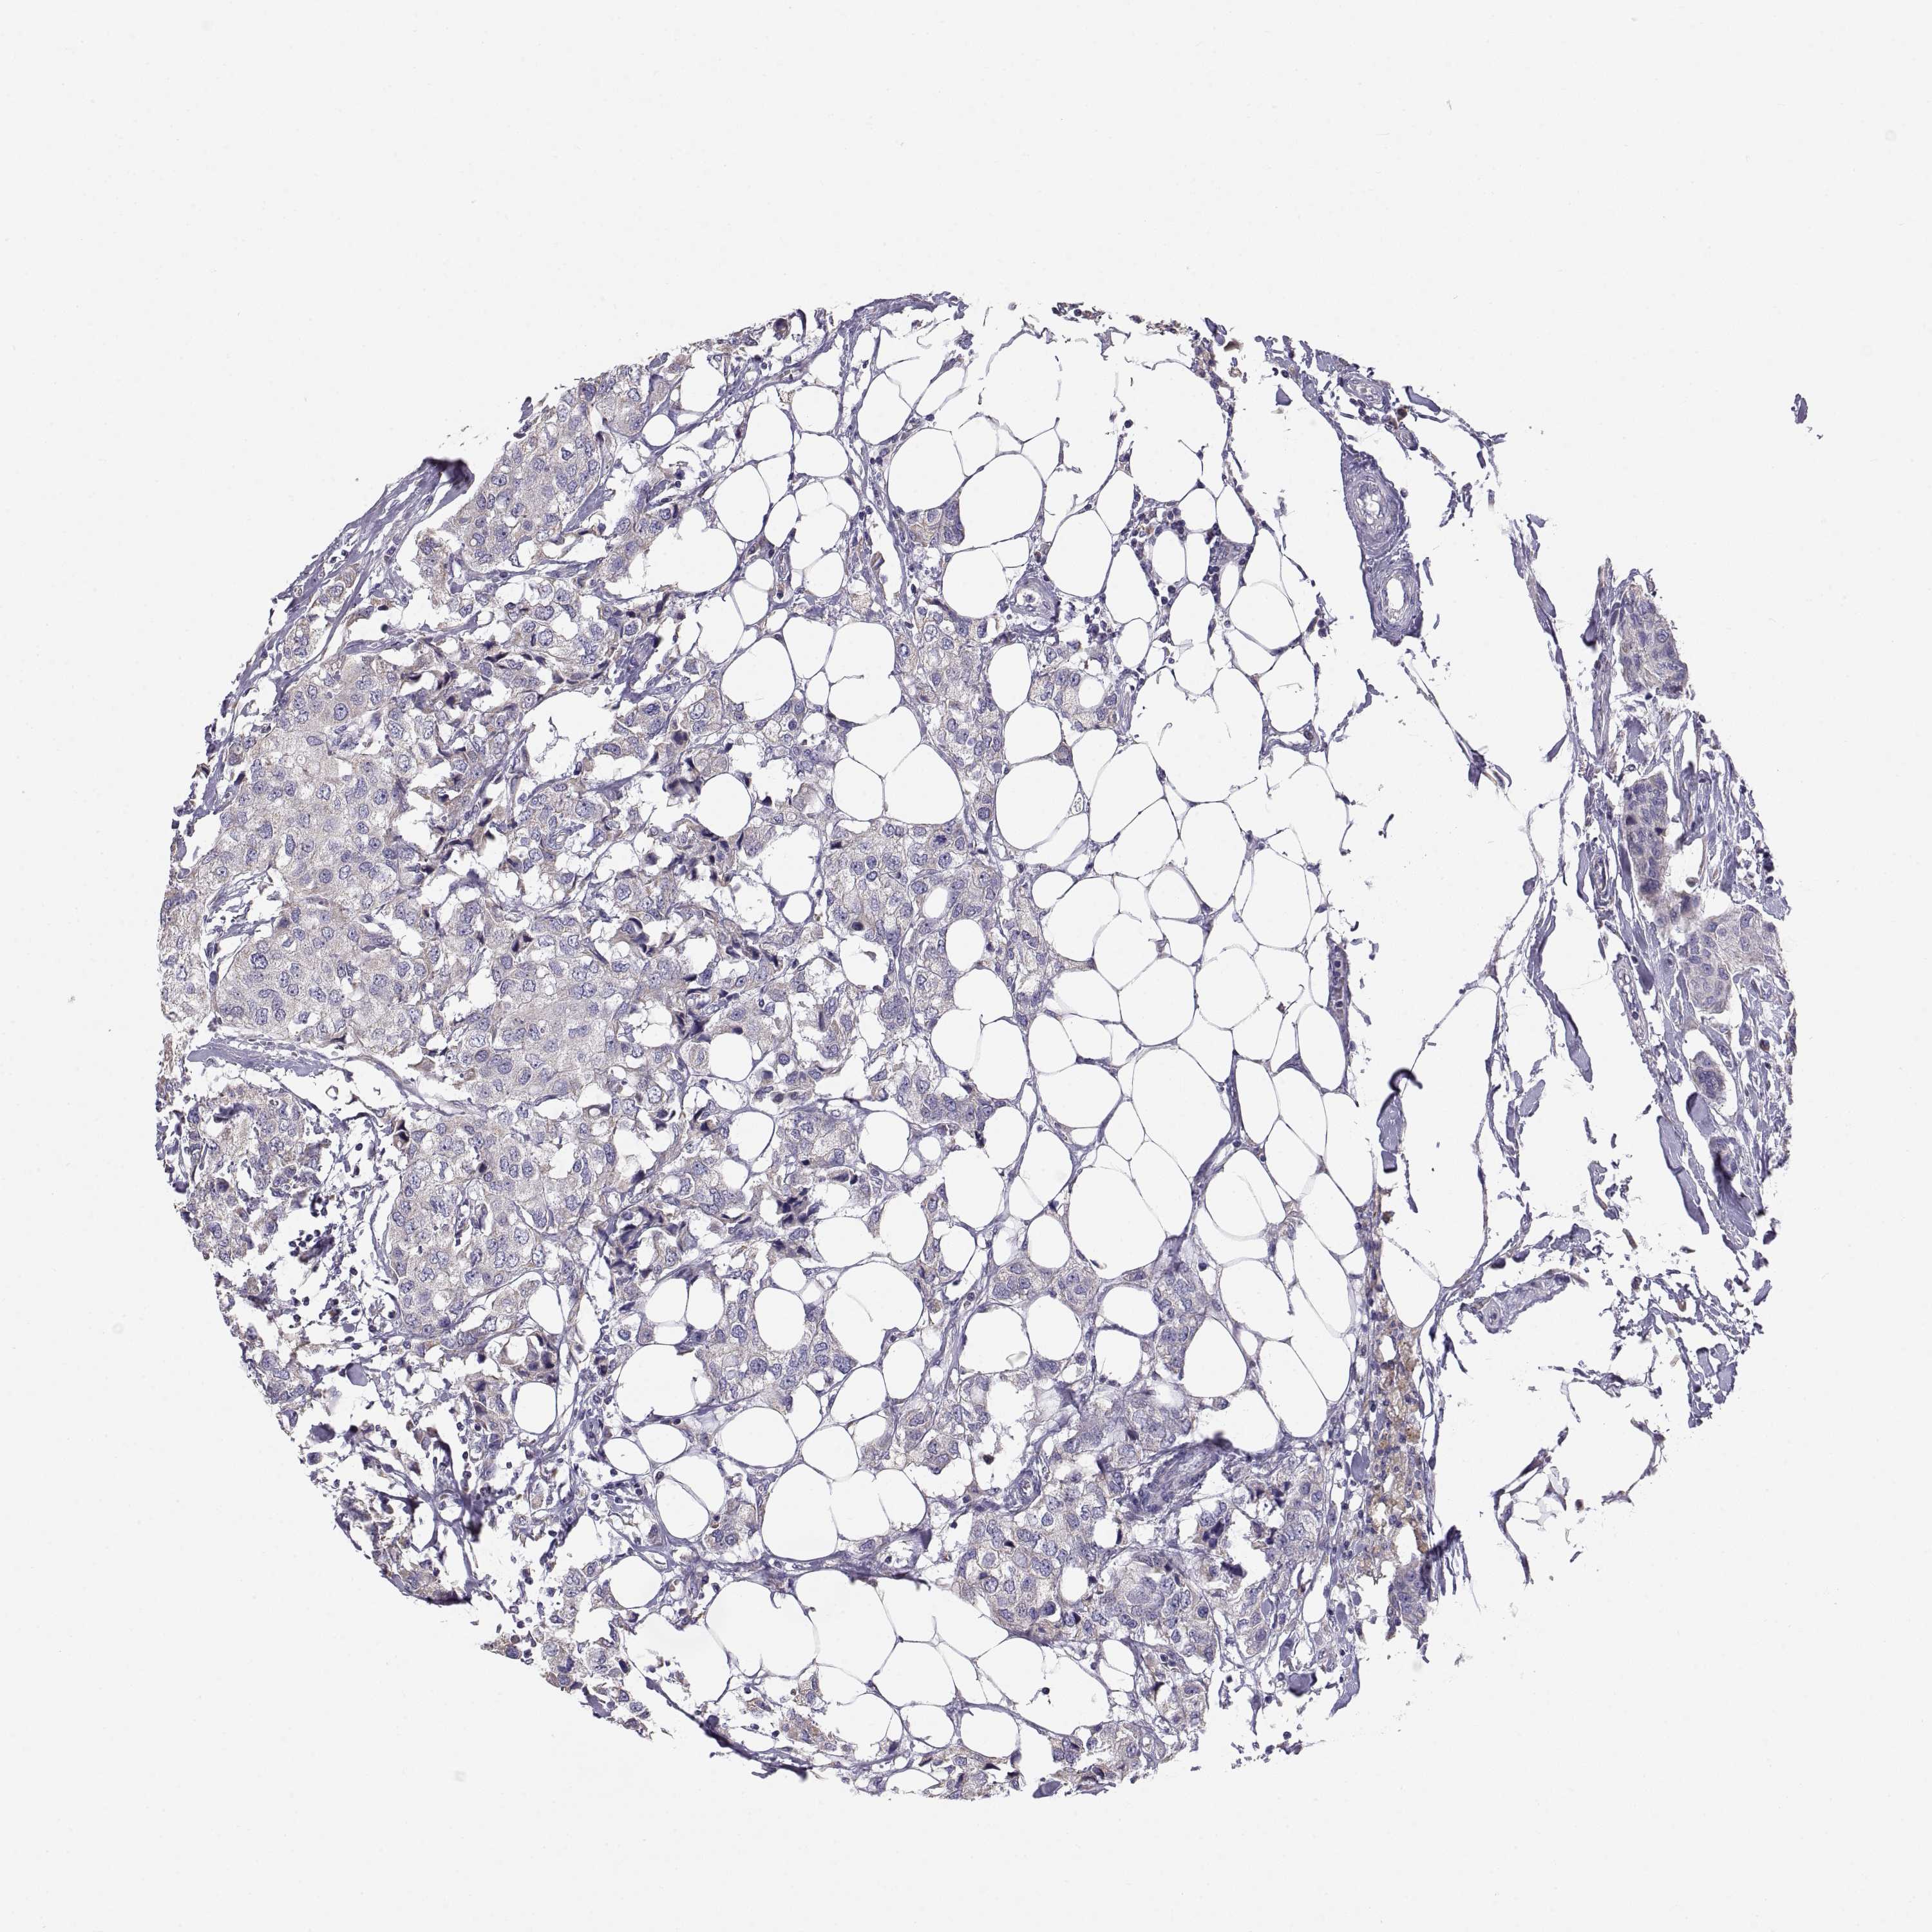

CANCER BREAST CANCER Show tissue menu

BRCA TCGA BRCA VALIDATION PROTEIN EXPRESSION